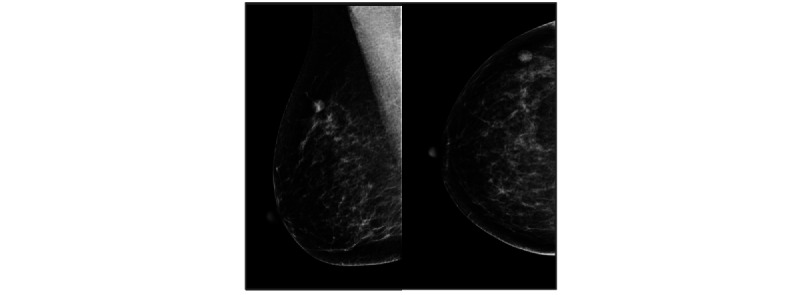

Methods: This is a retrospective study applying a commercial AI CAD system (Insight MMG, version 1.1.4.3; Lunit Inc) to a cancer-enriched mammography screening data set of 10,889 women (median age 56, range 40-74 years). The AI CAD generated a continuous prediction score for tumor suspicion between 0.00 and 1.00, where 1.00 represented the highest level of suspicion. A binary read (flagged or not flagged) was defined on the basis of a predetermined cutoff threshold (0.40). The flagged median and proportion of AI scores were calculated for women who were healthy, those who had a benign biopsy finding, and those who were diagnosed with breast cancer. For women with a benign biopsy finding, the interval between mammography and the biopsy was used for stratification of AI scores. The effect of increasing age was examined using subgroup analysis and regression modeling.